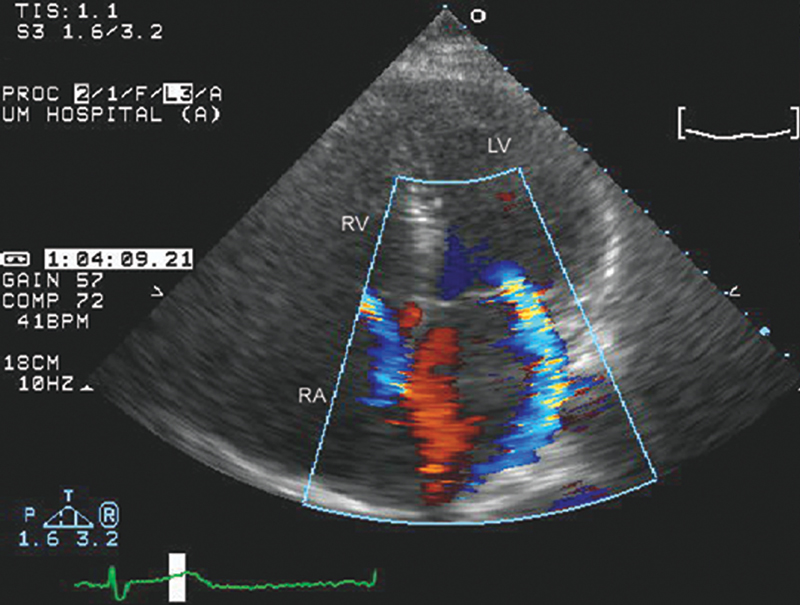

فحوصات تشخيصية لبعض امراض القلب والشرايين التاجية